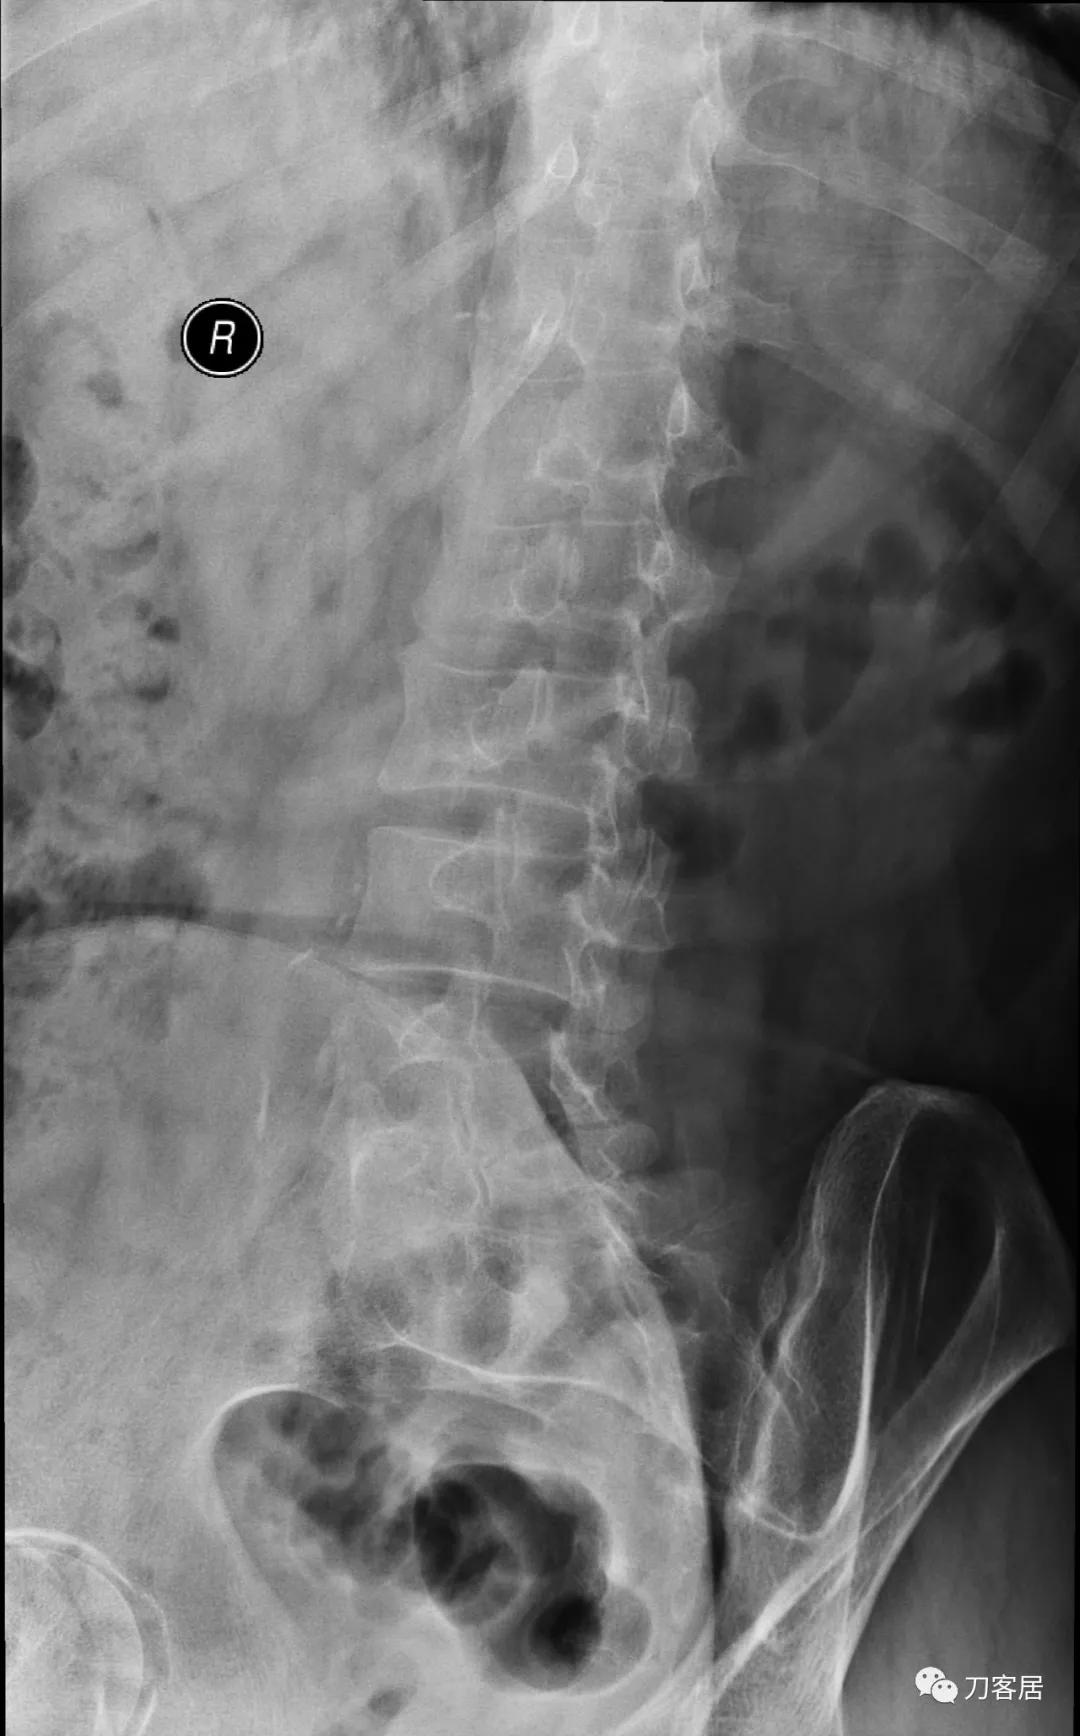

自带影像学检查提示腰5椎体前滑脱,腰5峡部裂,椎管狭窄不严重。

诊断:腰5峡部裂,腰5椎体前滑脱1度,骨质疏松症。

图3. 20210616术前腰椎正位X线片

图7. 20210616术前腰椎右斜位X线片

图8. 20210616术前腰椎左斜位X线片